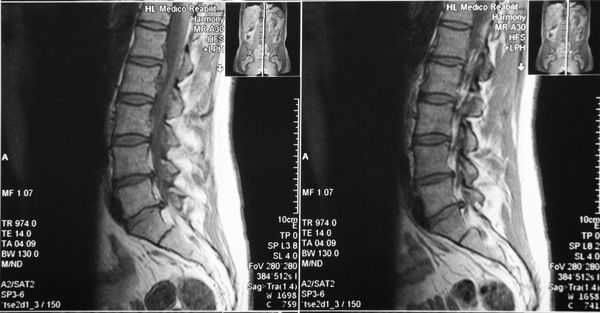

Вертеброгенные нарушения беспокоят длительное время. В связи с последним обострением — прострелом и болью в правой ноге — с 19.11.2018 года до момента поступления проходил лечение в поликлинике и в стационаре по месту жительства, но без существенной динамики: болевой синдром уменьшился, отмечаются чувствительные нарушения, снижение силы в правой стопе, вертебральный синдром и нарушение походки из-за болей. По данным МРТ пояснично-крестцового отдела позвоночника (ПКОП) от 23.11.2018 года, наблюдается МР-картина дегенеративно-дистрофических изменений сегментов ПКОП, медиальная грыжа L4-L5 и L5-S1 позвонков, относительный спинальный стеноз позвоночного канала на уровне сегмента L4-L5. Направлен на хирургическое лечение в указанную Дорожную клиническую больницу для оперативного лечения.

Функциональная спондилография поясничного отдела от 12.02.2019: остеохондроз II степени; спондилоартроз; нестабильность сегментов на уровне L4-L5 и L5-S1; ретролистез — смещение L5 позвонка назад — I степени. Электронейромиография (ЭНМГ) от 12.02.2019: малоберцовые нервы в норме с обеих сторон; признаки заинтересованности корешков L4-S1 справа. Мультиспиральная компьютерная томография (МСКТ) ПКОП от 13.02.2019: КТ-картина дегенеративно-дистрофических изменений поясничного отдела позвоночника; большая задняя срединная грыжа межпозвонкового диска на уровне L4-L5 позвонков с абсолютным стенозом спинального канала; задние диффузные протрузии дисков L5-S1 и умеренная протрузия уровня L2-L3. МРТ ПКОП от 14.02.2019: МР-картина дегенеративно-дистрофических изменений сегментов ПКОП; задняя медианная экструзия (выбухание) диска L4-L5 с признаками компрессии корешков конского хвоста и вторичного дурального стеноза на уровне L4-L5 на 2/3; протрузии дисков L2-L3 и L5-S1; ретролистез L5 I степени.

Диагноз

Остеохондроз пояснично-крестцового отдела позвоночника. Дискогенная радикулопатия L5 справа, обусловленная секвестрированной парамедианной транслигаментарной грыжей диска L4-L5 с компрессией L5 корешка и абсолютным стенозом позвоночного канала. Выраженный стойкий болевой и миотонический синдром.